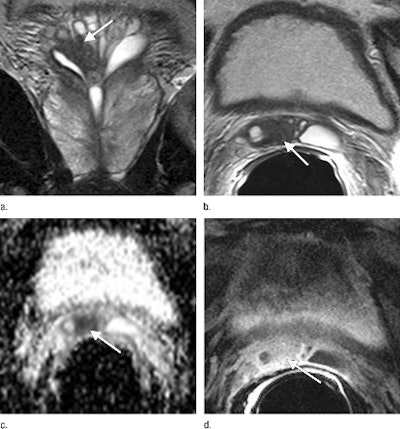

| The surgical plan for this 53-year-old man was changed to a non-nerve-sparing technique after review of coronal (a) and axial (b) T2-weighted images that show a low-signal-intensity mass (arrow) extending into the right seminal vesicle. Apparent diffusion coefficient map (c) shows restricted diffusion (arrow), corresponding to the low-signal-intensity focus on T2-weighted images. Contrast-enhanced fat-saturated T1-weighted gradient-echo image (d) shows enhancing nodule (arrow), corresponding to the area of low signal intensity on T2-weighted images. Images courtesy of Radiology. |

Of 173 sides in which nerve-sparing surgery was initially planned, 168 (97%) were stage T2 cancer, according to MRI results. The specificity of prostate MRI in differentiating T2 disease from T3 disease was 98%.

"This suggests that, in our patient population, if a patient's prostate MR image shows T2 disease, a nerve-sparing technique can be used with a high degree of safety and without compromising oncologic outcome," the authors wrote.